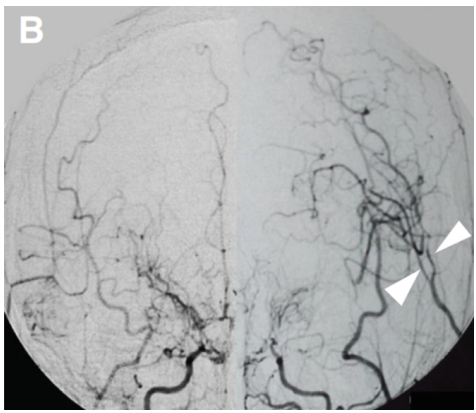

术后20天血管造影显示旁路通畅(箭头)。